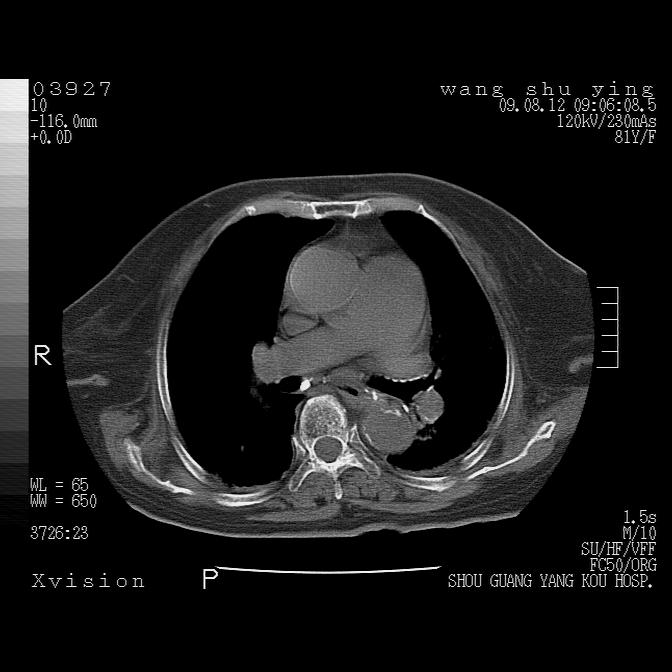

以下是引用帅河马在2009-8-12 12:59:00的发言:[br]两肺感染性病变伴双侧胸膜肥厚。[br]左侧甲状腺腺瘤不除外。[br]腹水+心包积液。[br][br][本贴已被 帅河马 于 2009-8-12 13:14:32 修改过]

以下是引用sdzyy在2009-8-12 18:17:00的发言:[br]两肺感染性病变伴双侧胸膜肥厚。[br]左侧甲状腺腺瘤不除外。[br]腹水+心包积液。[br]支持

以下是引用随光逐影在2009-8-12 19:42:00的发言:[br]1)两肺感染性病变伴双侧胸膜肥厚。2)不排除左侧甲状腺腺瘤。3)肝脏占位性病变;建议行进一步检查。